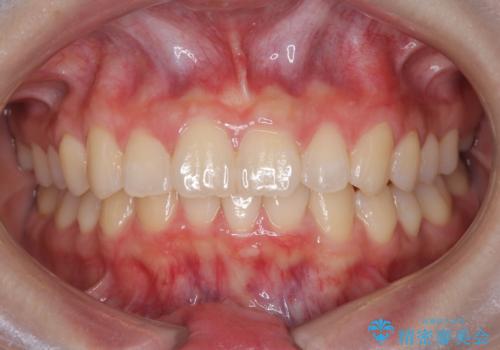

今回は抜歯矯正ではなく歯列弓の拡大とIPR、遠心移動を行って配列することができました。

口元も改善し患者さんには喜んでいただけました。

下顎前歯が1本少ないため、上下の正中は合いません。